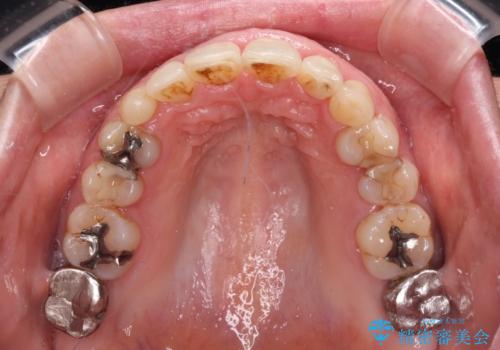

口元の出っ張りとデコボコを改善したい

近医での歯周病治療の影響でブラックトライアングルが発現していたため、IPR(歯と歯の間を削る)で隙間を改善しつつ、インプラントを固定源に歯列全体を後方へ移動させることとしました。

インプラントは矯正治療では動かすことができないため、インプラント治療を行う前に矯正治療を行う意思があるのかを確認します。

特に出っ歯などで抜歯矯正となる場合には、インプラントが邪魔になることがあるので注意する必要があります。